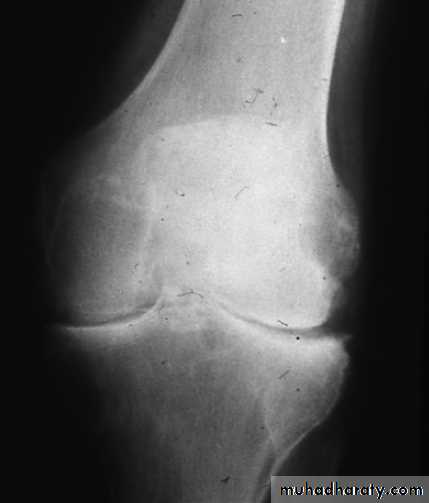

X-ray appearances in knee osteoarthritis. There is almost complete loss of joint space affecting both compartments,

And sclerosis of subchondral bone.